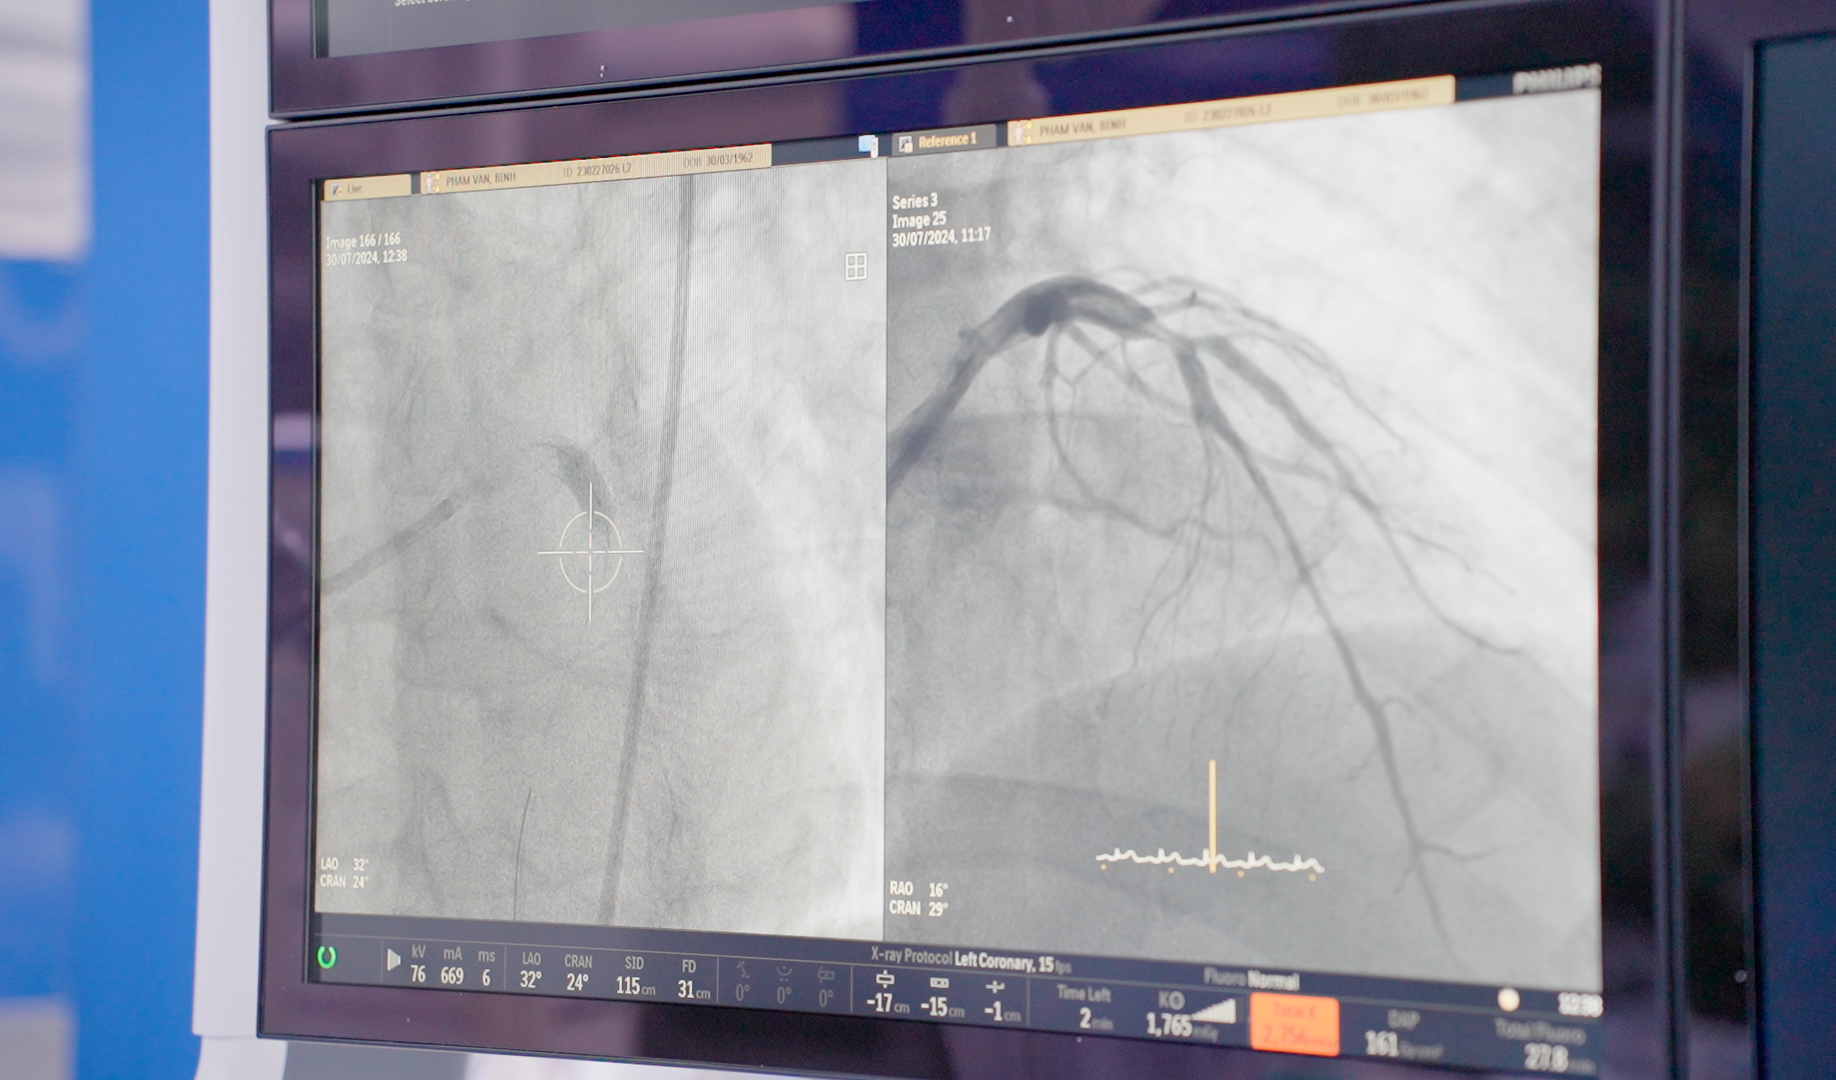

Tình trạng trước và sau khi can thiệp thành công bằng kỹ thuật nong bóng phủ thuốc cho bệnh nhân bị hẹp mạch vành nặng tại BVĐK Hồng Ngọc